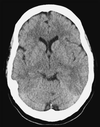

What is the diagnosis

Identify the arrowed features on the scan

SAH with evidence of hydrocephalus

- Blood in sulci

2 + 3: Frontal and occipital horns of the lateral ventricles are dilated as is the third ventricle (4)

There is intraventricular blood (5)

The low-denstry area around the frontal horn represents transependymal flow (6) due to acute hydrocephalus

Blood is seen in the right sylvian fissure, 7, and in the interpeduncular cistern, 8 and the right and left, 9 10, ambient cisterns.

The quadrigeminal cistern 11 is clear of blood.

The temporal horns of the lateral ventricles are dilated